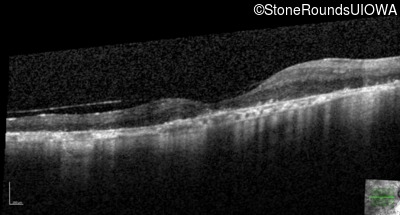

Age at visit: 63 years